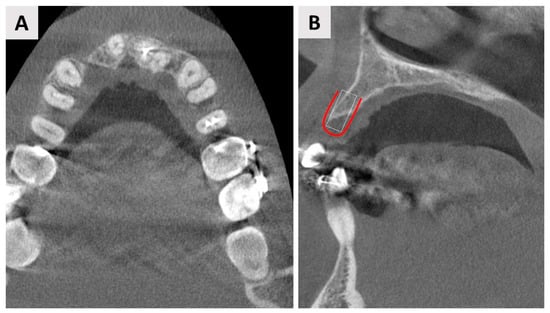

4. Case Report Two: GBR with Immediate Implant Placement